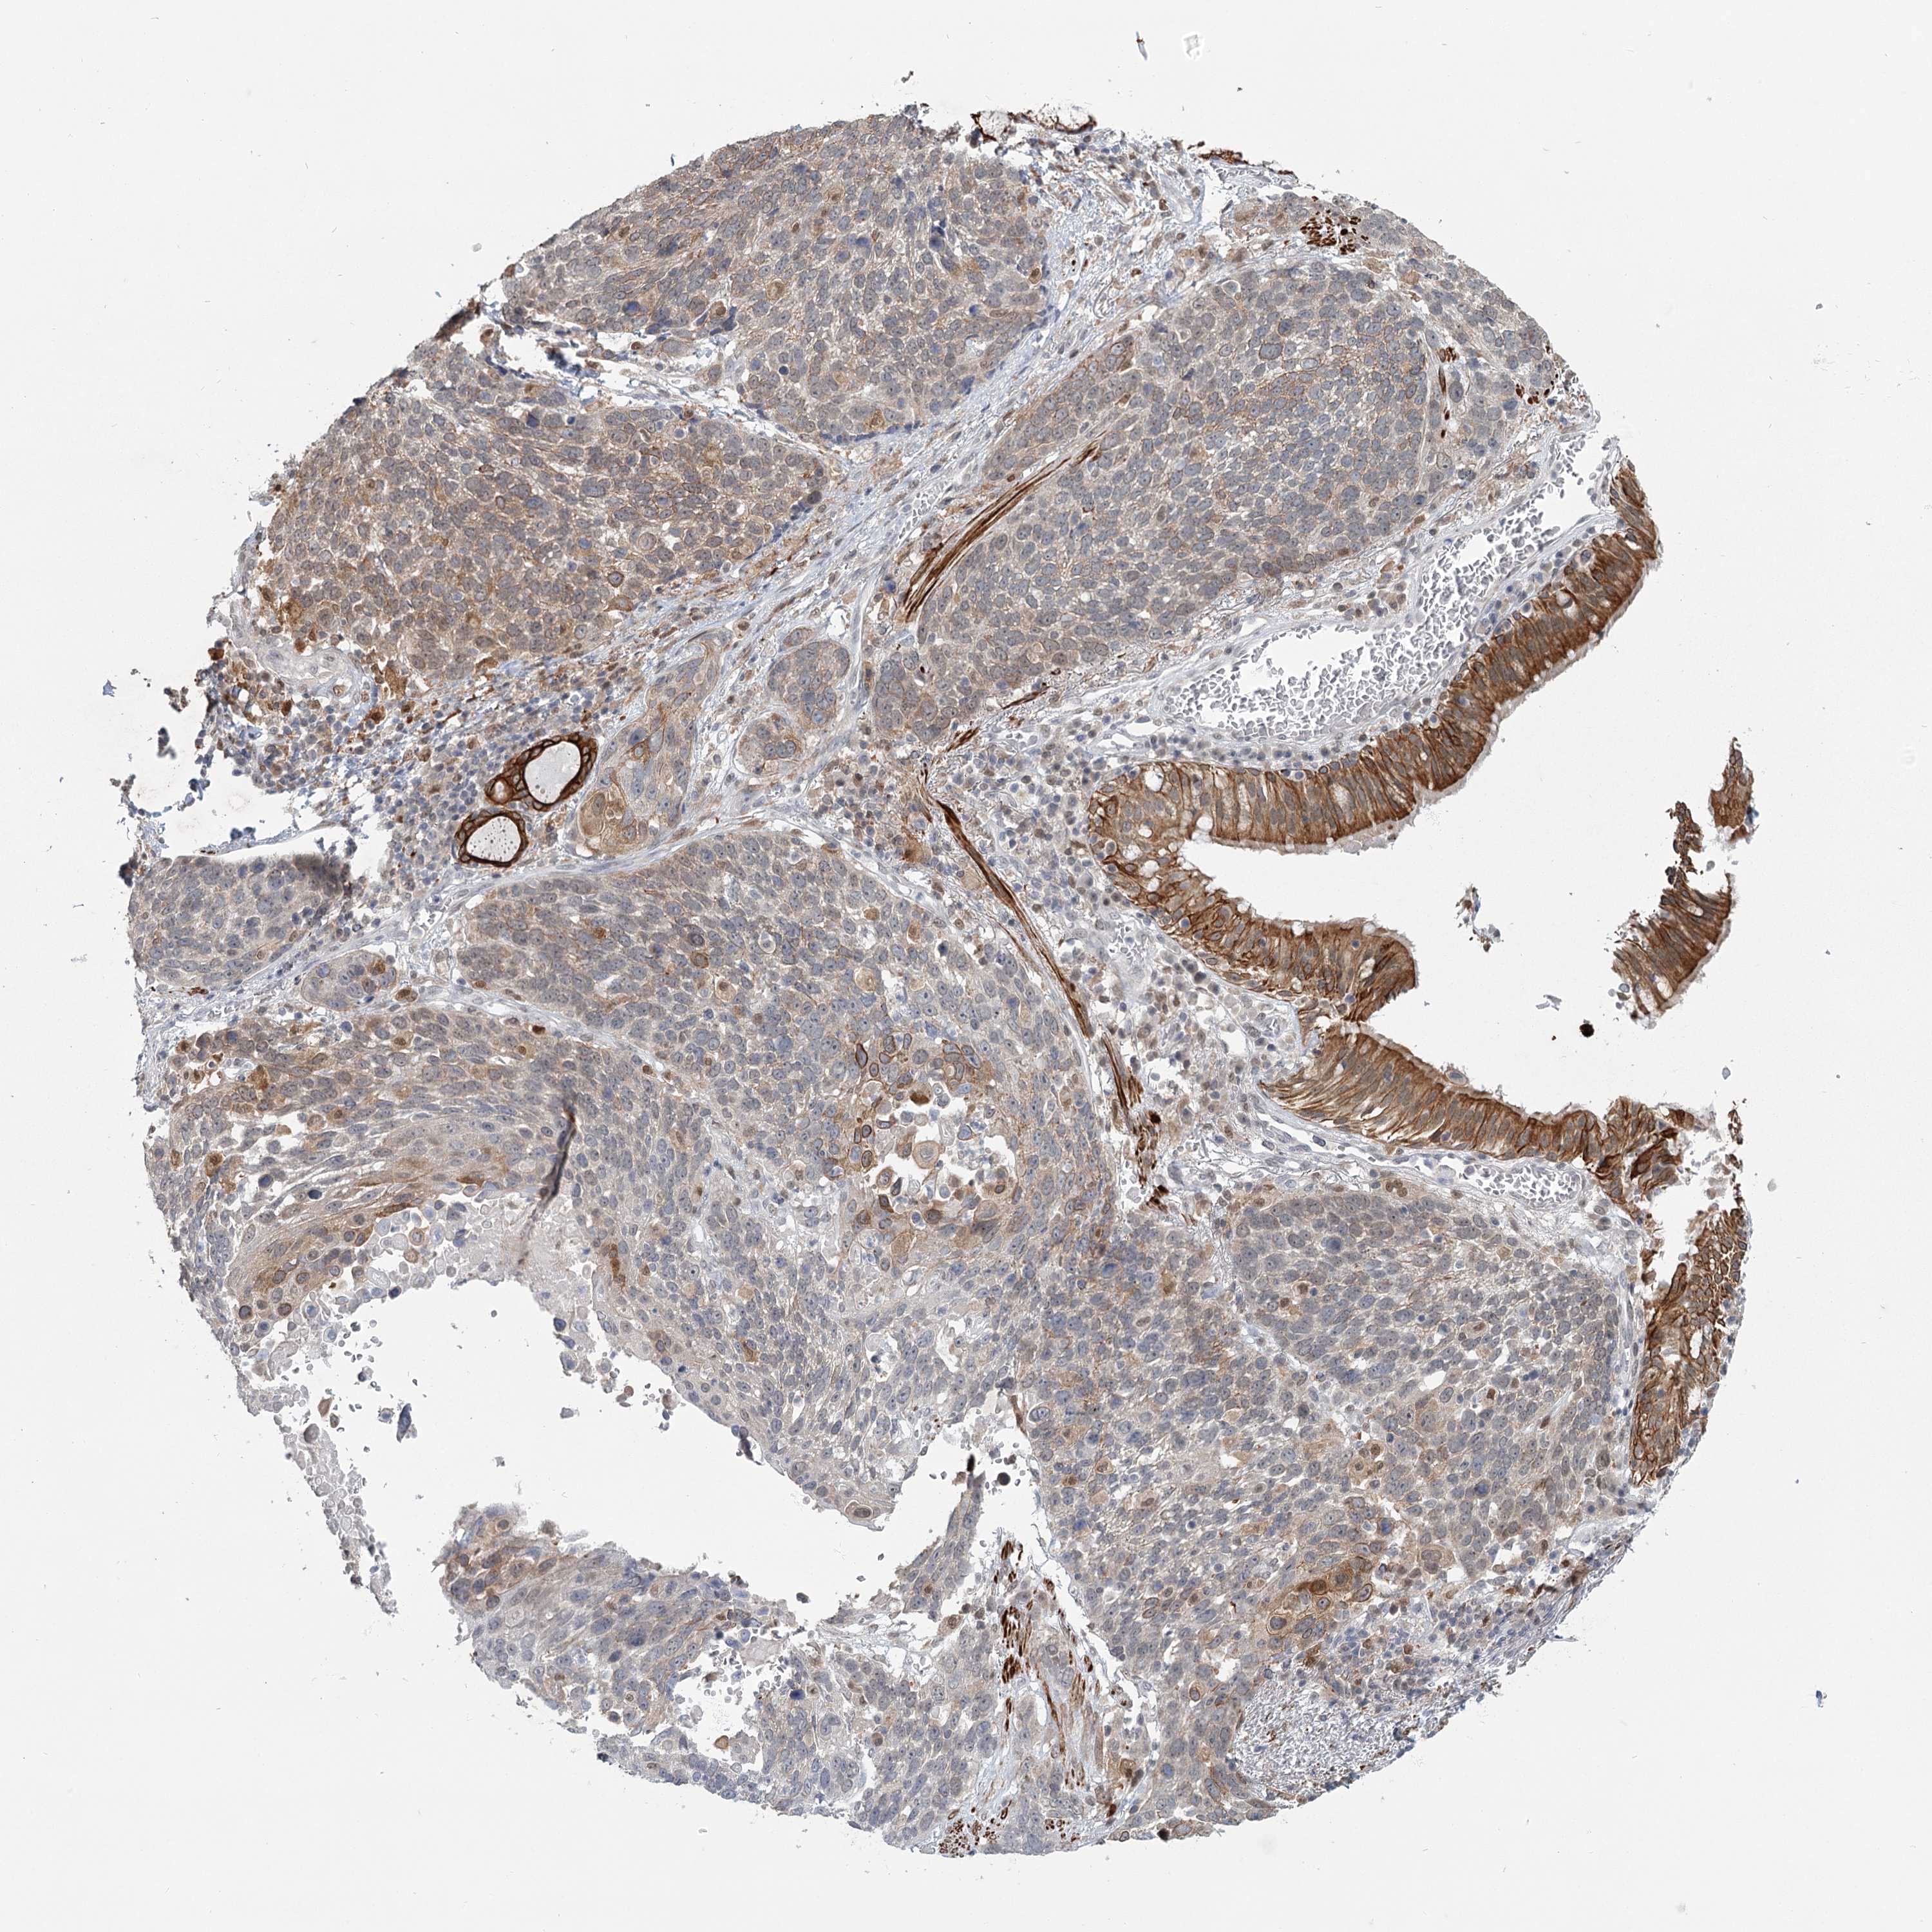

CANCER LUNG CANCER Show tissue menu